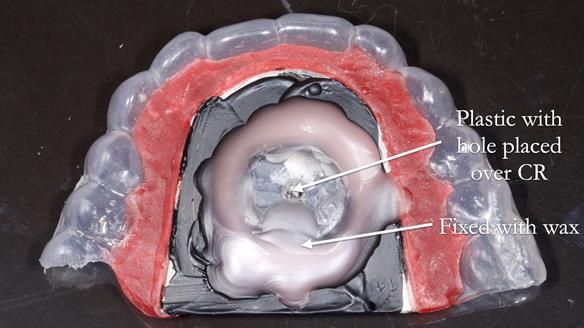

However, once Rowan and I reviewed the remaining metal crown on tooth 46, we realised it would make an ideal abutment for a gasket denture. By reshaping the lingual surface of the crown, we created an excellent gasket seal.

This approach worked far better than the proposed ring-clasp design - improving retention, comfort, and aesthetics while keeping the design clean and simple.

- The gasket seal around 46 was made using retention.sil 200, producing a precise, cushioned fit.